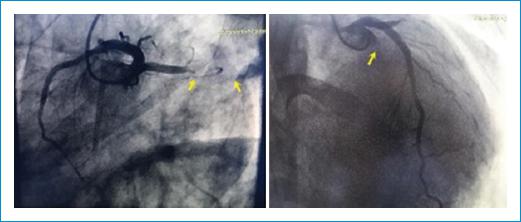

Fue ingresado en la unidad de cuidados coronarios, donde se documentó choque cardiogénico que requirió ventilación mecánica invasiva. La troponina I fue > 30. Posteriormente se realizó ecocardiograma, en el que se diagnosticó insuficiencia de válvula mitral grave, jet excéntrico que llegaba hasta las venas pulmonares, insuficiencia aórtica moderada, fracción de eyección del ventrículo izquierdo del 45%, ventrículo izquierdo moderadamente dilatado y ventrículo derecho hipertrófico. Luego, mediante cateterismo cardiaco, se observó oclusión total de la arteria circunfleja en su porción proximal (Fig. 1).